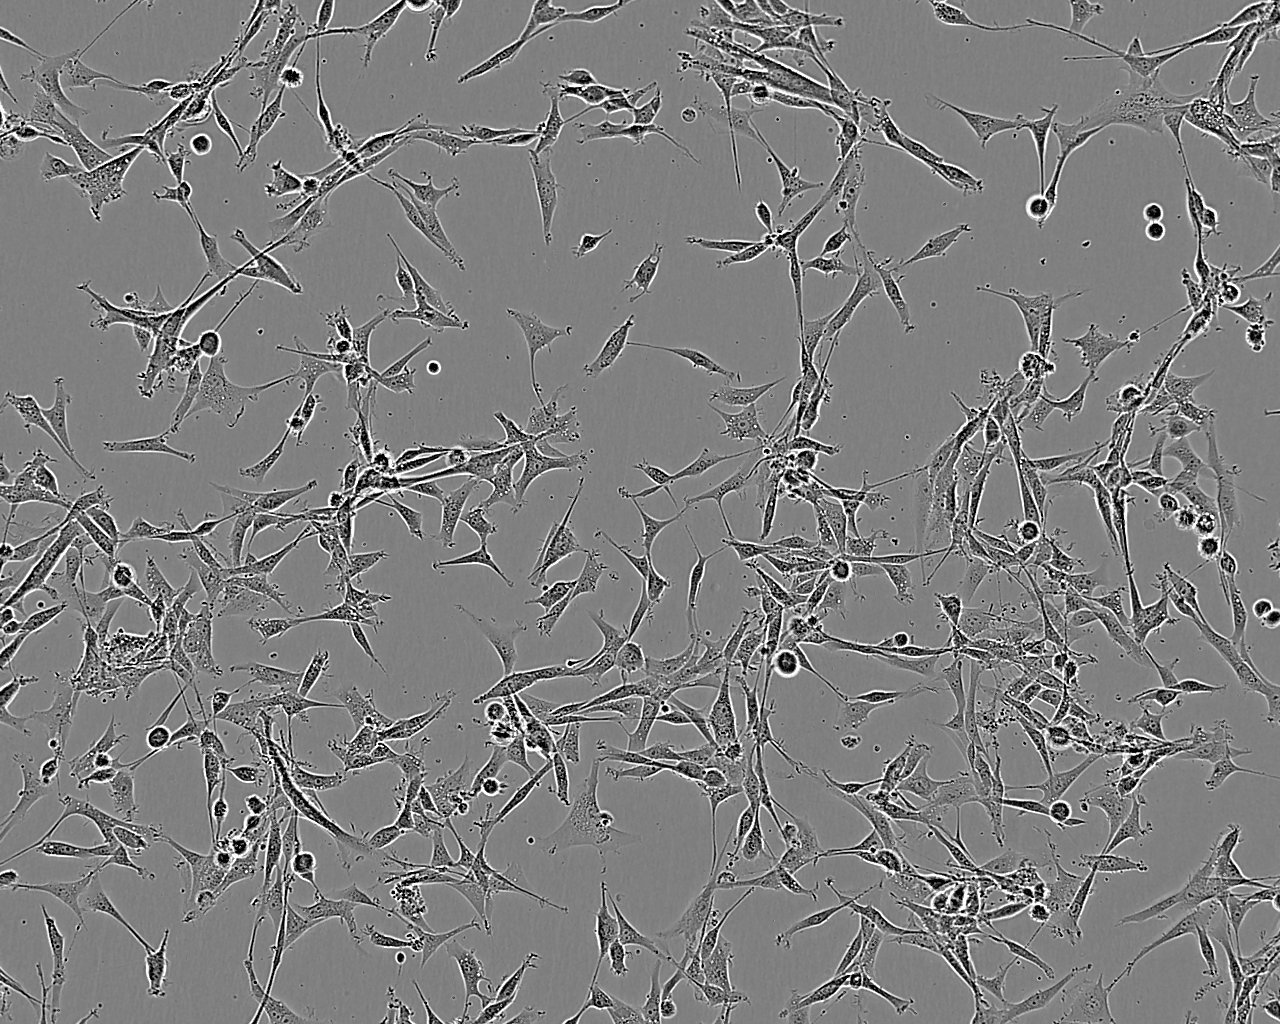

细胞背景资料:该细胞系源于一位60岁的白人女性患者的肺腺癌组织。

细胞形态:上皮细胞样

细胞生长:贴壁

细胞生长特性:贴壁生长

细胞形态特性:上皮细胞样